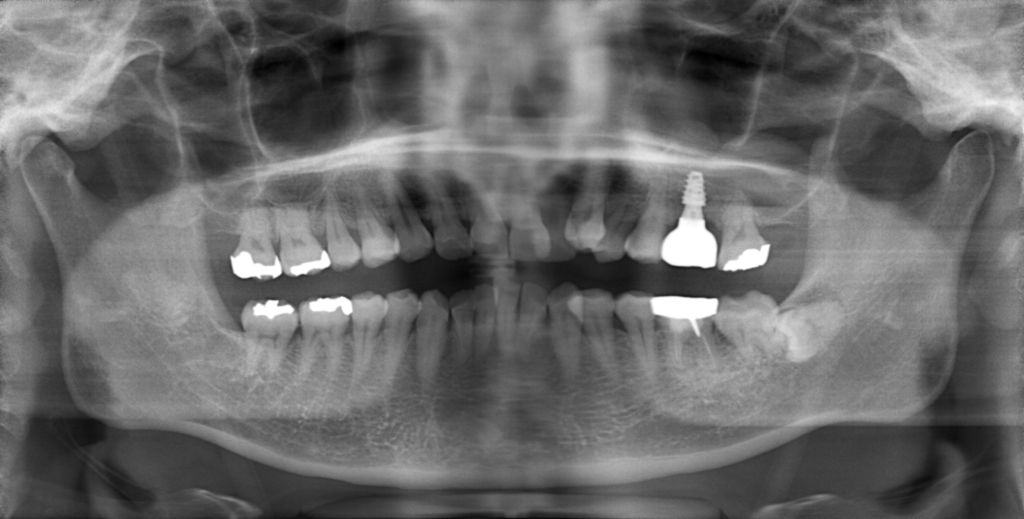

前歯の4本が、残すのが難しい状況となり、インプラント治療を行いました。

インプラントは前歯に2本埋入し、4本の前歯を作っています。歯を抜くと同時にインプラントを埋入し、仮歯を作りました。その後2ヶ月で、被せ物を入れました。被せ物は、セラミックスで作っています。

治療前

治療後